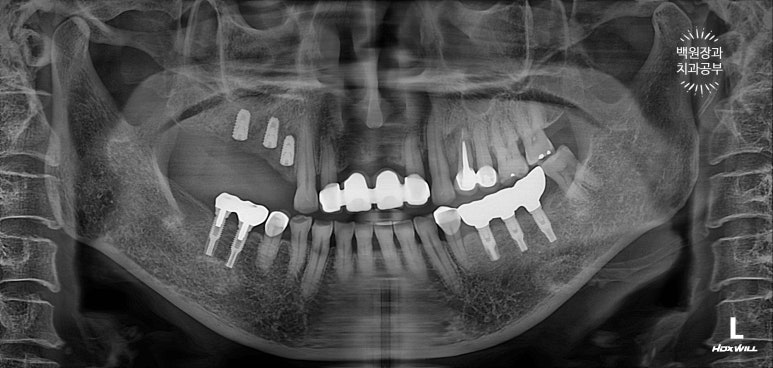

뼈이식을 하고나서 촬영한 치과용 파노라마 사진입니다.

뼈이식재가 엄청나게 잘 위치된 것을 볼 수 있습니다. 마치 뼈가 하나도 없어지지 않았던 것처럼......

기억하셔야 할 점은 이 재료들이 100프로 뼈가되지 않는다는 것입니다. 그래서 더 비싸고 좋은 뼈이식재료를 사용하는 치과를 찾아가셔야 합니다. 아무래도 좋은 재료일수록 잘 버티고 많이 남죠....

정확히 4개월을 기다려 임플란트를 심어드렸습니다.

보시면, 처음 뼈이식했던 것보다는 임플란트가 다소 깊이 위치한 것을 보실 수 있죠?

왜냐면, 아까 얘기했듯이 우리가 사용했던 뼈이식재가 100프로 모두 잇몸뼈가 되지 않기 때문이죠.